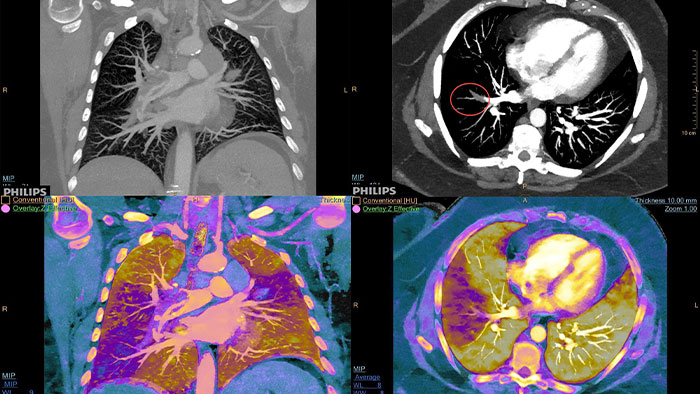

Allez plus loin que l'imagerie conventionnelle. Constatez par vous-même la pertinence de l'imagerie spectrale à la détection pour améliorer votre confiance diagnostique.

Voir la différence entre le scanner conventionnel et la détection spectrale